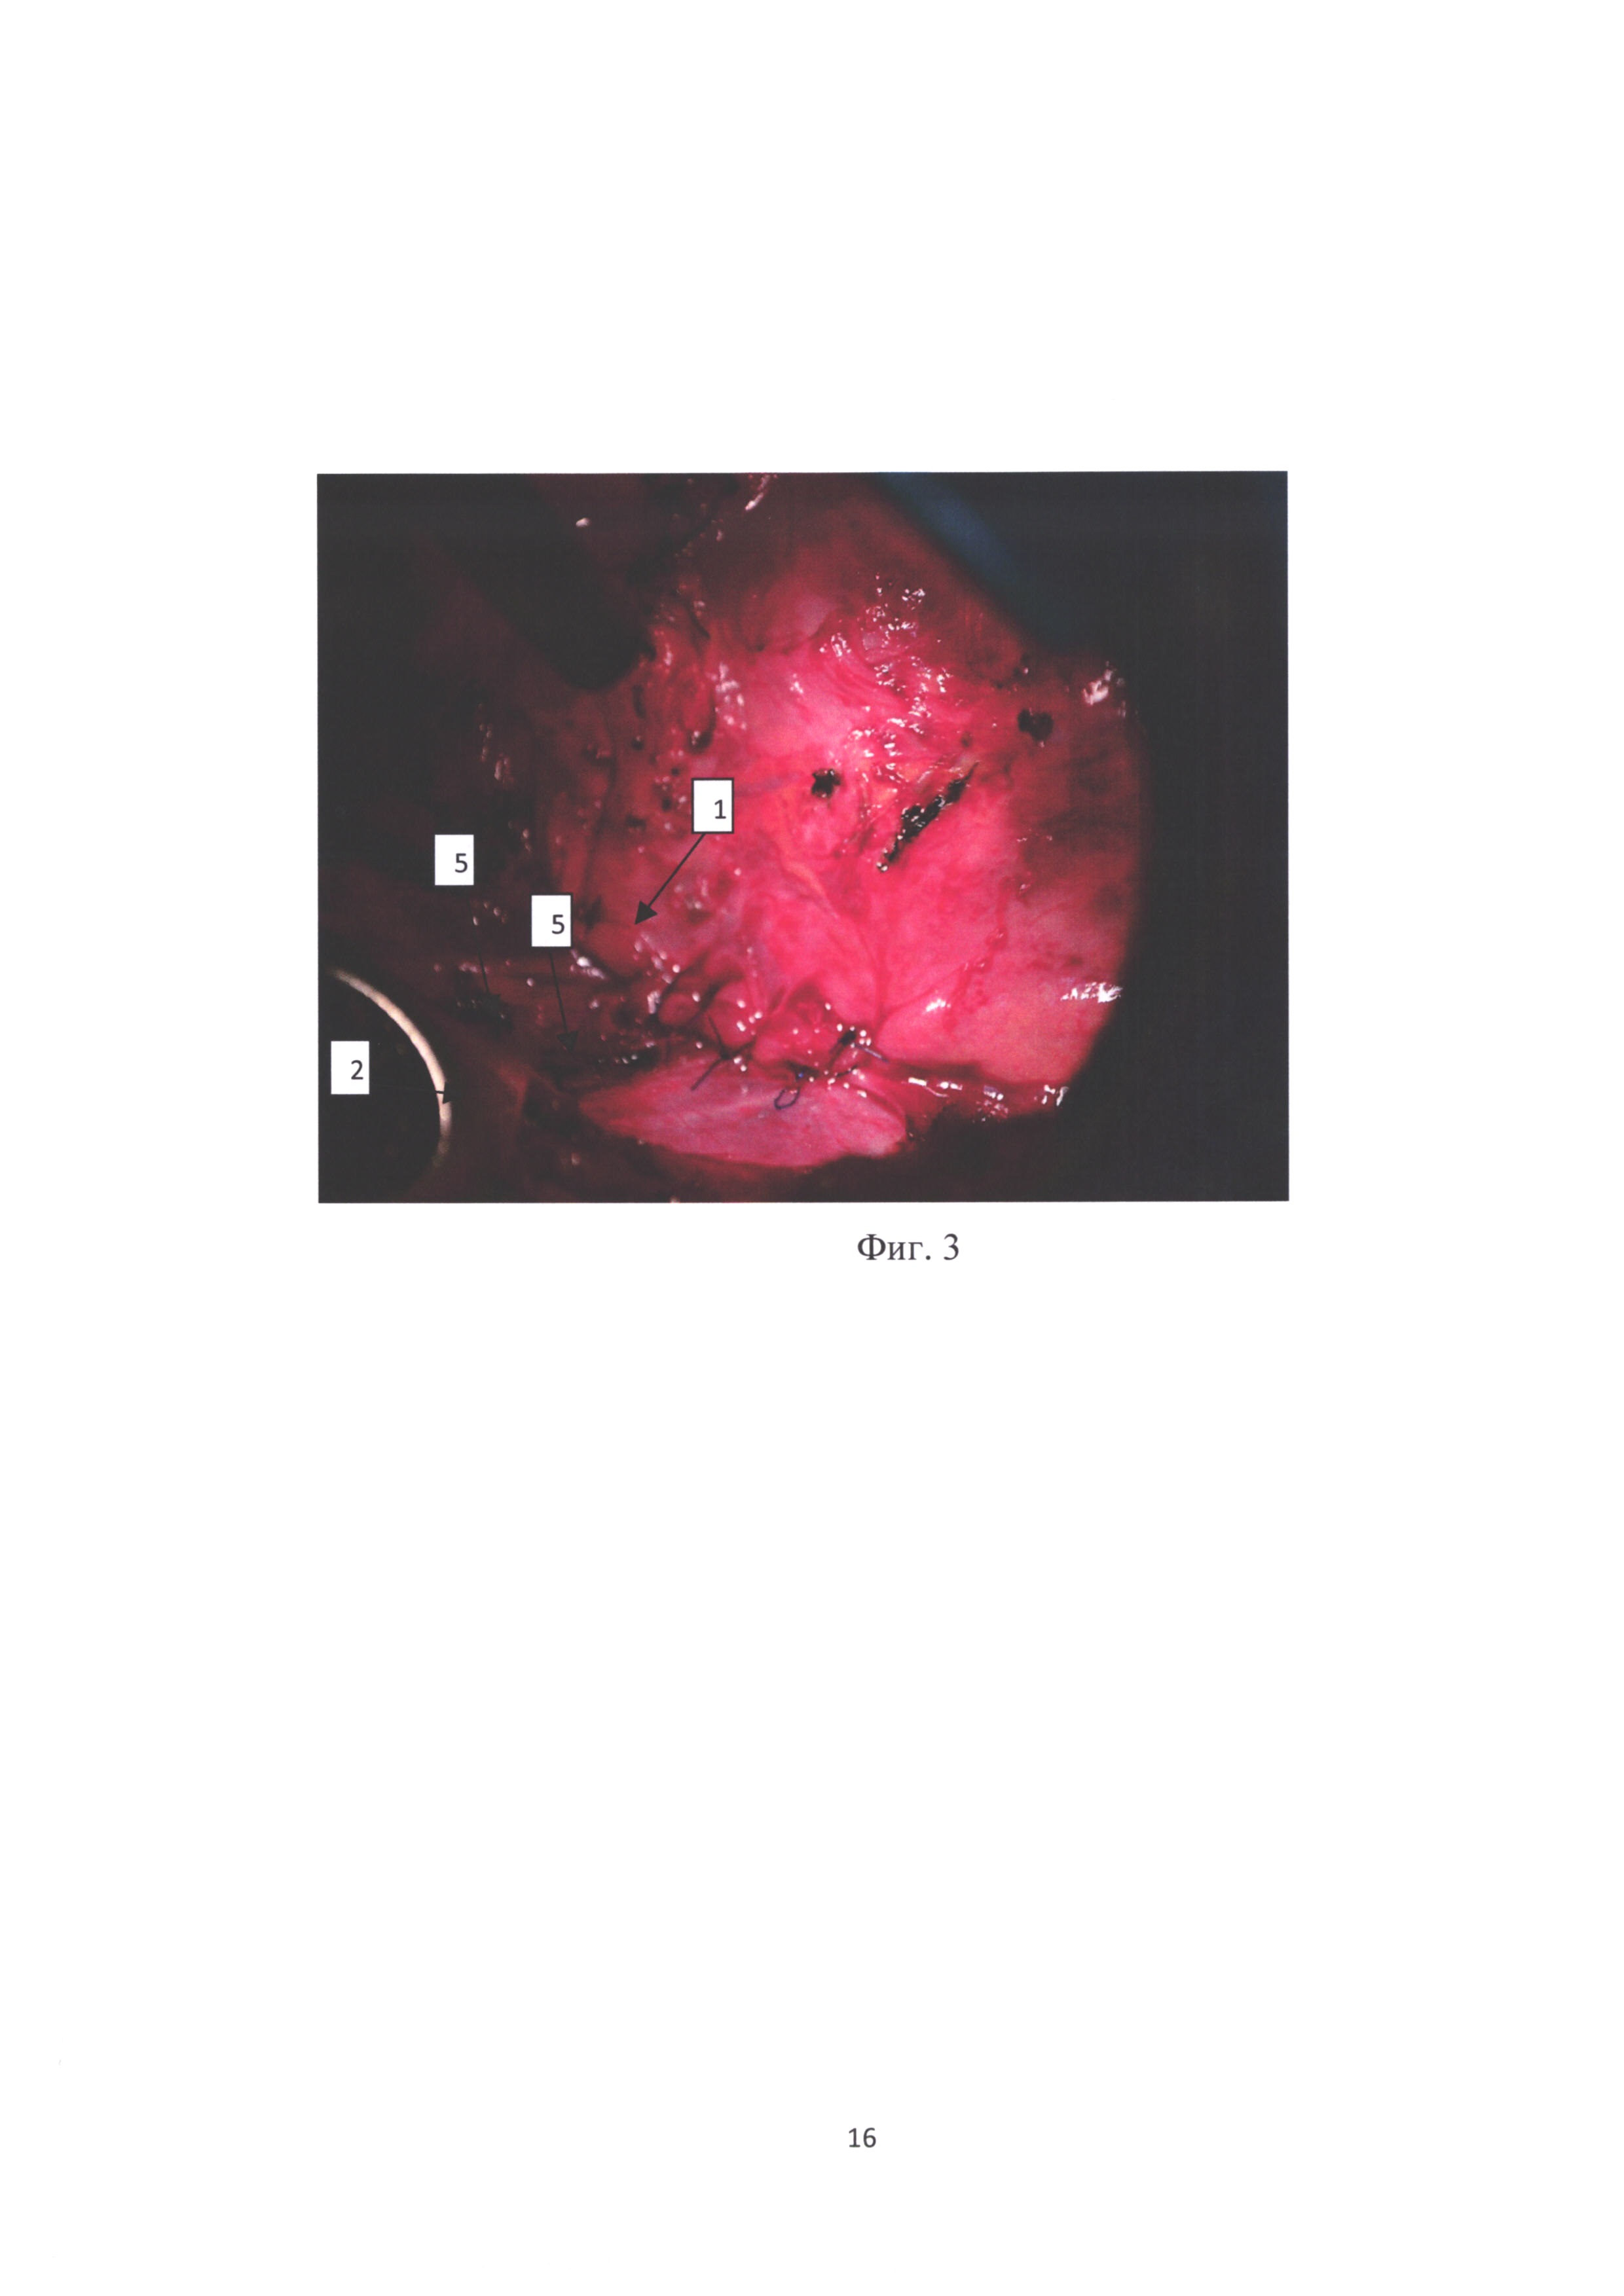

фиг. 1 - переднее средостение после удаления легкого с обозначением границы грыжевых ворот;

[31]

На чертежах обозначены:

[34]

1 - перикард, 2 - передняя грудная стенка, 3 - грыжевые ворота, 4 - грыжевой мешок, 5 - швы после медиастинопластики.

Выполняются последовательно следующие операции, которые иллюстрируются фото, представленными на фиг. 1-3.

[37]